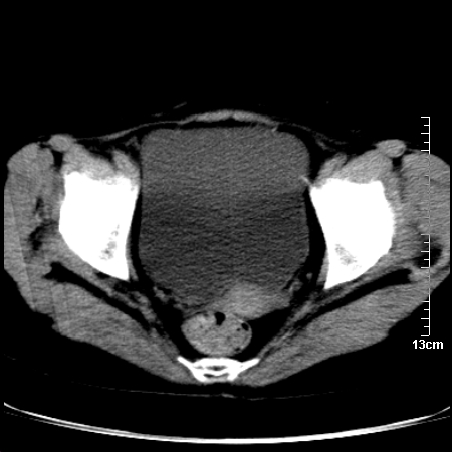

术前的疏忽,手术前诊断阑尾炎,但是没有常规做b超,导致术后1周检查发现 1。实性包块?2。腹腔术后脓肿?

病史:病人一周前诊断阑尾炎,未做b超,手术发现阑尾化脓,(没有留意有无包块),术后1周病人发热,血象:1.6万,做b超发现,随ct检查,上传图片

巨大囊实性包块,边界大部尚清楚,不太像脓肿的表现。应该做个增强检查除外盆腔肿瘤。

脓肿可能性大. 因回盲部区域化脓性兰尾切除残端感染改变征像与实性肿块关系密切.肿块上界至右下腹,下界至盆腔膀胱上缘, 如果是实性肿块在兰尾术中可能就会发现. 所以术后一周病人高烧, 白细胞增高,临床表现支持脓肿.

盆腔一边界大部份清晰囊实性肿块,其周腹脂未见确切异常,其一端与右侧附件相连。考虑右侧附件肿瘤。

如果能进行肠道准备就好了!盆腔内巨大囊实性包块,右前缘与周围肠管分界不清,病灶内前部的气体是否为肠管内气体形成的假象不能确定。

这么大一包快手术当中没有发现?值得怀疑!结合化脓性阑尾炎病史,首先考虑脓肿!不排外附件来源的肿瘤,建议增强扫描!!